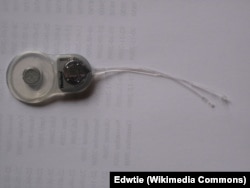

Создание полностью искусственного глаза – дело будущего, а заменить электроникой слуховой нерв можно уже сегодня. Такая система разработана в США: микрофон улавливает звук, затем сигнал поступает в носимый за ухом микрокомпьютер, где трансформируется в цифровой сигнал и достигает собственно импланта, который в свою очередь напрямую стимулирует преддверно-улитковый нерв, отвечающий за передачу слуховых импульсов.